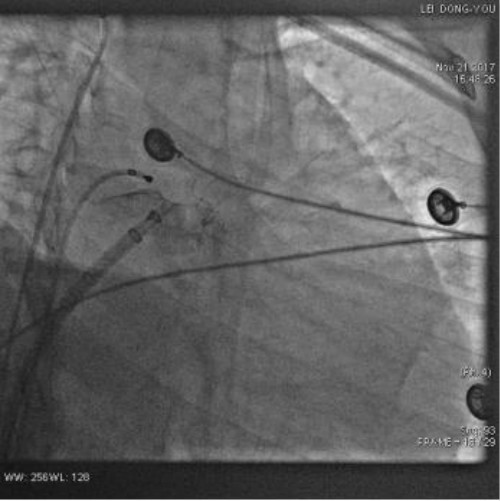

经过精心充足准备,在院领导的支持下,11月21日在麻醉科、超声科、器械科、介入室等科室大力配合下,王洪主任带领的电生理团队在外请专家方教授指导下成功给患者实施了冷冻球囊肺静脉电位隔离术和左心耳封堵术。手术历时3小时,在隔离左下肺静脉电位过程中房颤终止恢复窦性心律,然后用一枚直径30mm的Watchman封堵伞成功封堵左心耳,手术圆满成功。目前患者已经平安出院。